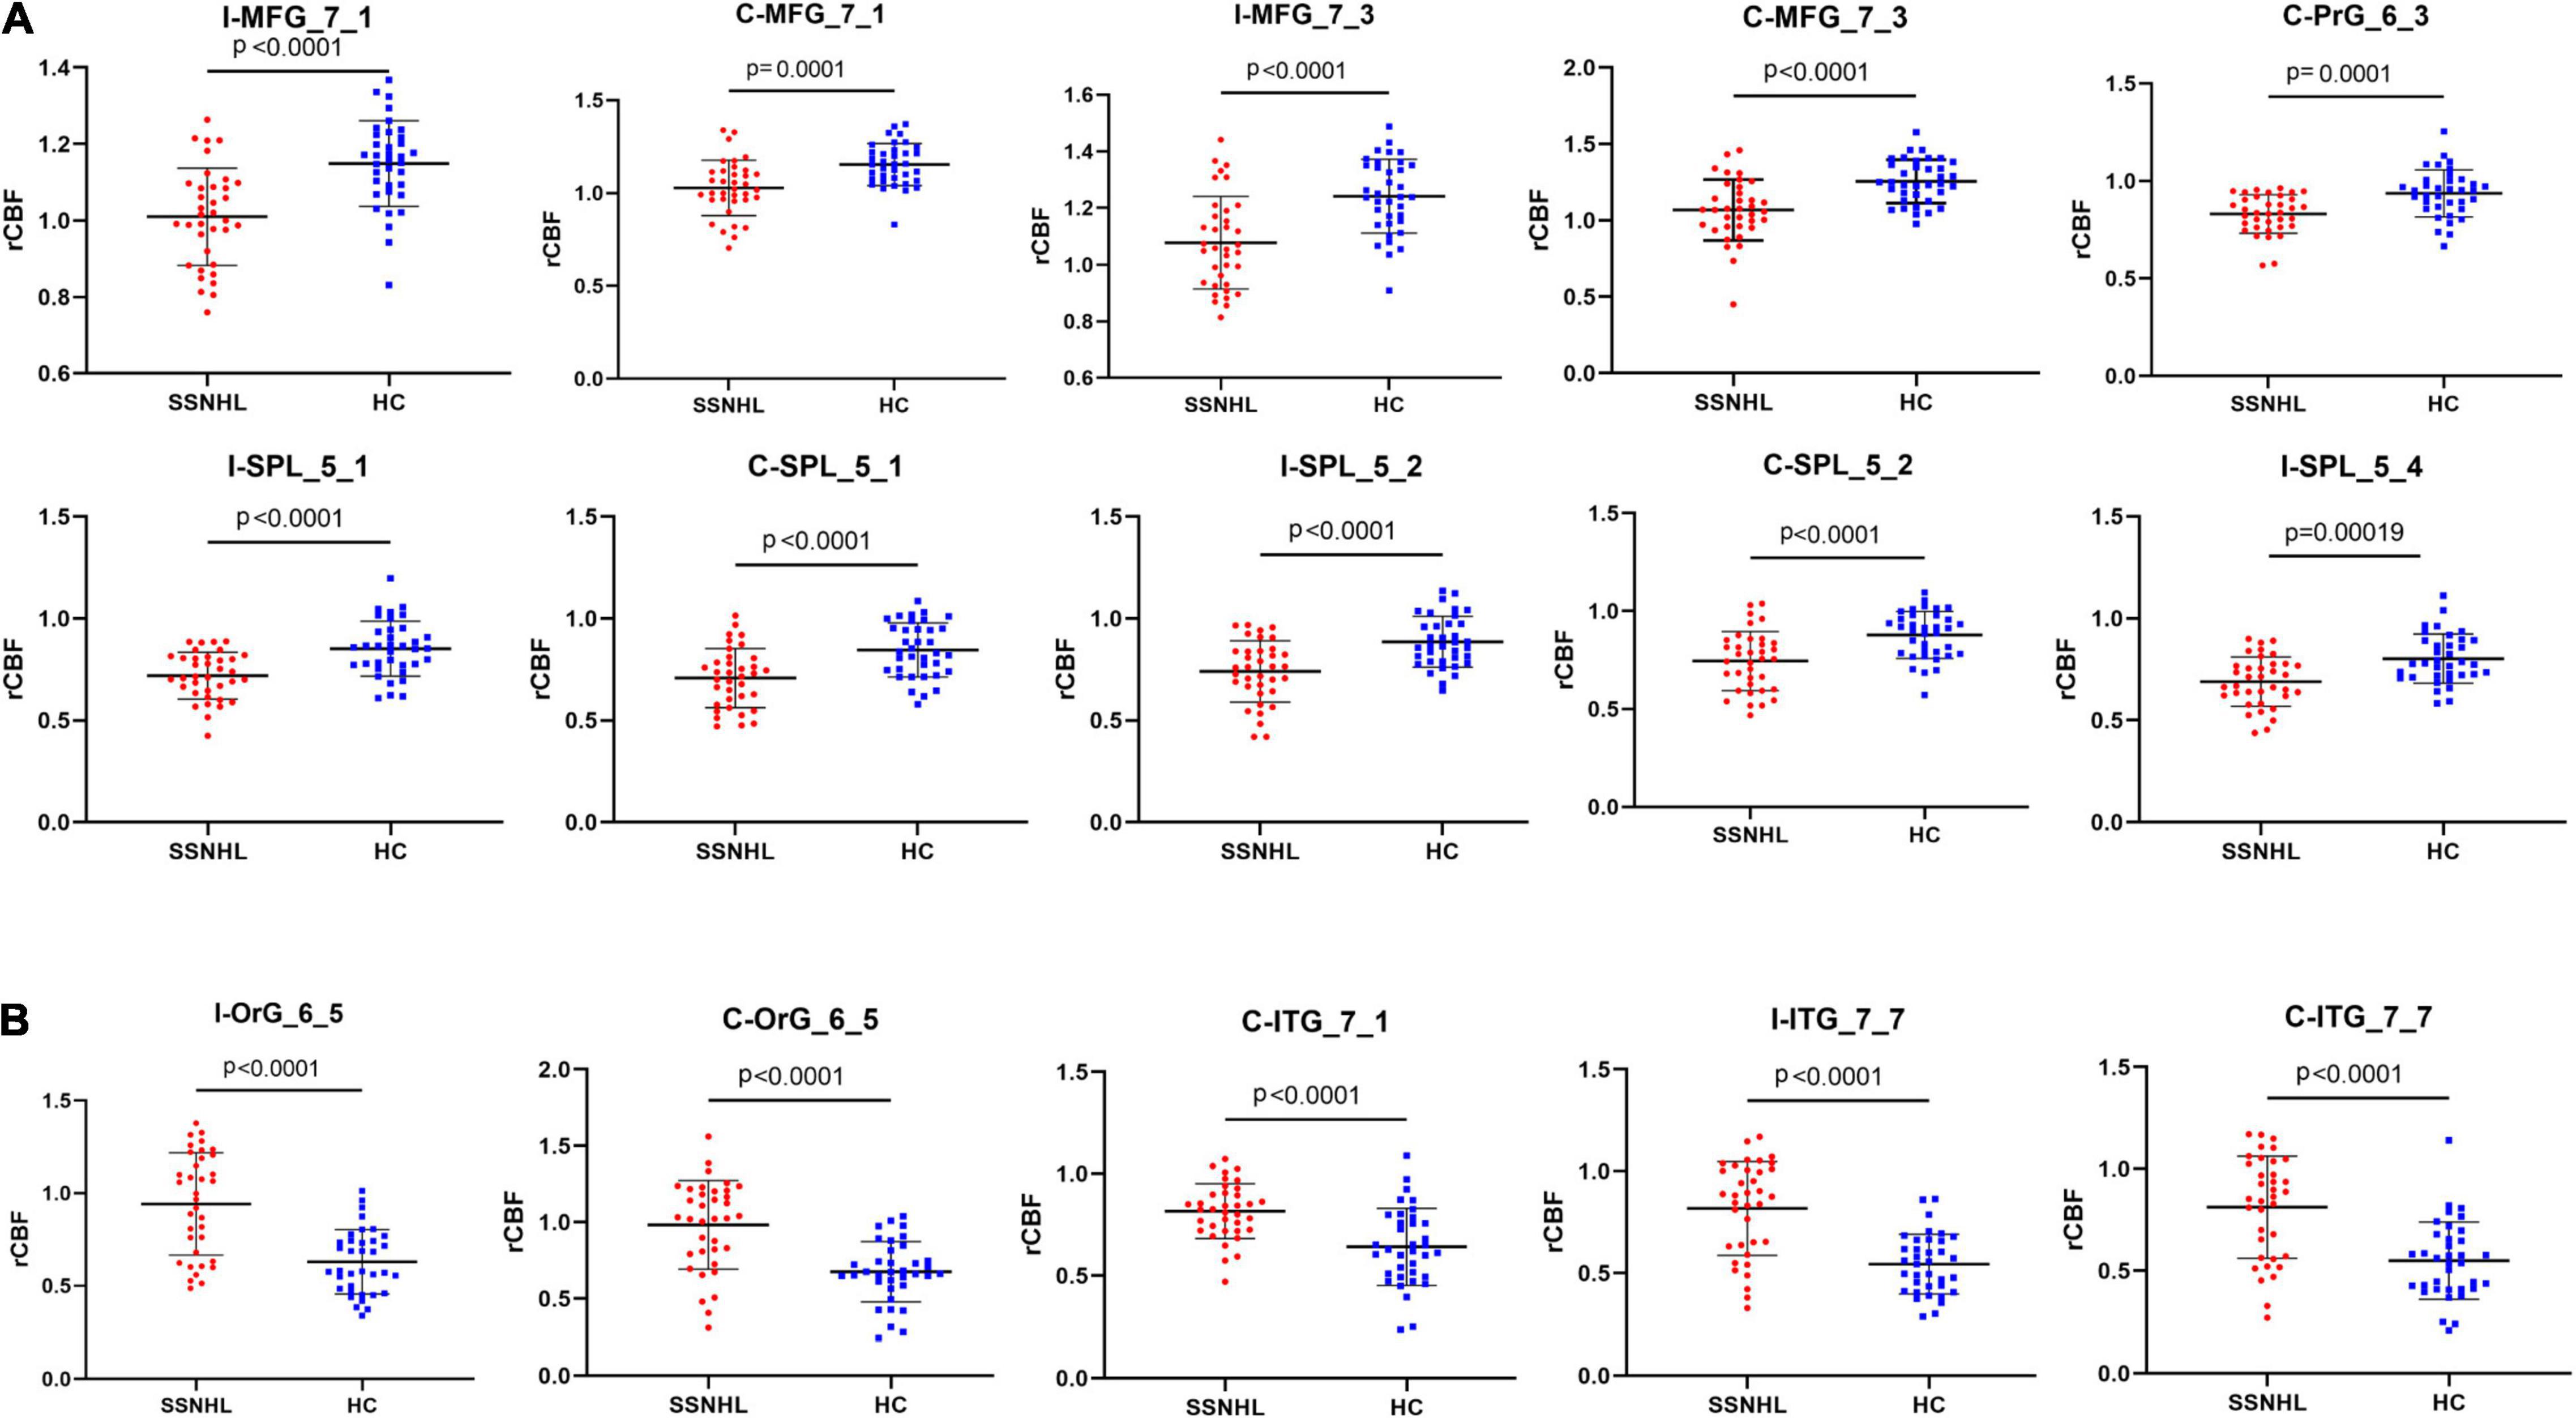

Results: The SSNHL patients exhibited decreased CBF in the bilateral middle frontal gyrus (MFG, MFG_7_1 and MFG_7_3), the contralateral precentral gyrus (PrG, PrG_6_3) and the bilateral superior parietal lobule (SPL, bilateral SPL_5_1, SPL_5_2, and ipsilateral SPL_5_4), p < 0.0002. Compared with HCs, unilateral SSNHL patients exhibited increased rCBF in the bilateral orbital gyrus (OrG, OrG_6_5), the bilateral inferior temporal gyrus (ITG, contralateral ITG_7_1 and bilateral ITG_7_7), p < 0.0002. lSSNHL showed abnormal CBF in left BA21 caudal (p = 0.02) and left BA37 dorsolateral (p = 0.047). We found that the CBF in ipsilateral MFG_7_1 of SSNHL patients was positively correlated with tinnitus Visual Analog Scale (VAS) score (r = 0.485, p = 0.008).

The SSNHL patients exhibited decreased rCBF in the bilateral middle frontal gyrus (MFG_7_1 and MFG_7_3), the contralateral precentral gyrus (PrG_6_3) and the bilateral Superior Parietal Lobule (bilateral SPL_5_1, SPL_5_2 and ipsilateral SPL_5_4), p < 0.0002 (Figures 4, 5A).

Figure 5. Comparisons of rCBF values between healthy controls and patients with SSNHL. (A) Decreased CBF subregions in patients with unilateral SSNHL compared with healthy controls. (B) Increased CBF subregions in patients with unilateral SSNHL compared with healthy controls. Data was mean ± SD. I, ipsilateral; C, contralateral; MFG, middle frontal gyrus; PrG, Precentral Gyrus; SPL, superior parietal gyrus; ITG, inferior temporal gyrus; OrG, orbital gyrus; SD, standard deviation.

Compared with healthy controls, unilateral SSNHL patients exhibited increased rCBF in the bilateral orbital gyrus (OrG_6_5), the bilateral inferior temporal gyrus (contralateral ITG_7_1 and bilateral ITG_7_7), p < 0.0002 (Figures 4, 5B).